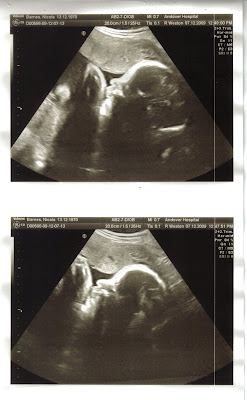

Scan went well I was worried about nothing. Yes I have slightly more fluid than average but its still within the normal limits. And yes baby is big lol, weighing in at approx 3 and a half pounds at the moment.

Was told everything looked good and it was a perfectly healthy baby.

Here's the pics :)

A foot!!!Waving lol.